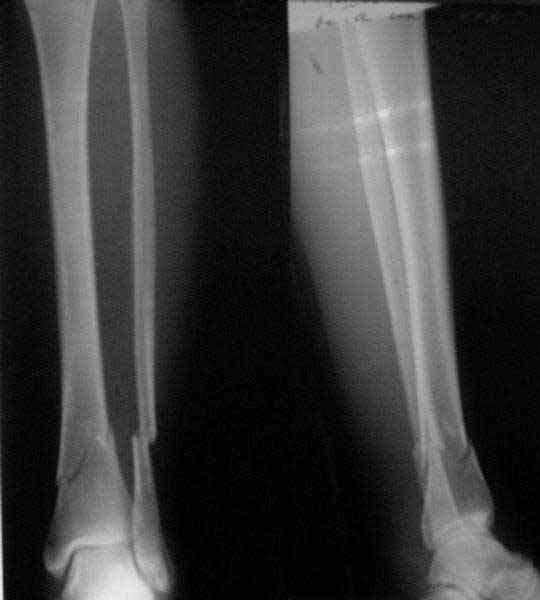

From the Xrays it seems as though the proximal fracture is relatively undisplaced. I thought that Poller screws were mostly used to prevent displacement of the fracture while the nail was being inserted. In this case I would think that you could hold the reduction temporarily either with a clamp, crossed K wires or a lag screw. Then insert the nail and place a proximal blocking screw only if you need to. Will the proximal locking screws fix the proximal fragment? Are you going to fix the fibula?

MC> From the Xrays it seems as though the proximal fracture is relatively

MC> undisplaced.

Yes.

The Poller screw here can easily lead to displacement because nail acts as a changing lever during insertion, and its angle to the shaft at initial and final postions are different. So the proximal fragment can be pushed backwards initially, then returned back - but likely with some residual displacement. So most reasonable are measures you mentioned:

Or by a small plate with monocrtical screws. My preference is a small wire distractor.

If locking screws are inserted usually it is unnecessary.

Depends on nail design. I am going to make an additional hole in the proximal nail end.

No. Why?